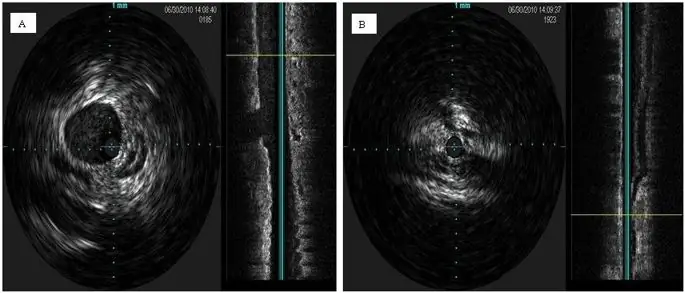

figure9

Пример внутрисосудистого УЗИ во внутренней яремной вене. Нормальный открытый просвет (A) и стенотический просвет (B) с фиброзной стенкой.